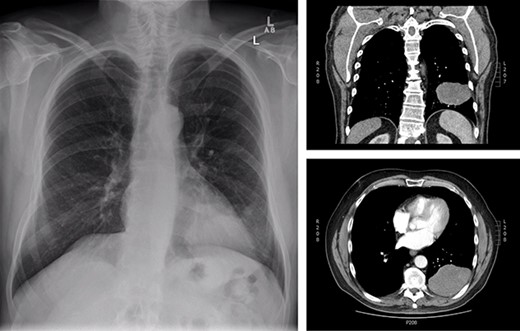

The patient is a 70-year-old man with a 75-pack-year smoking history and occupational asbestos exposure, who presented with back pain and constitutional symptoms in 2019. Physical exam was unremarkable except for hypertrophic pulmonary osteoarthropathy with digital clubbing. Computed tomography chest demonstrated a 18.3 × 17.0 × 13.8 cm left pleural-based tumour, with heterogeneous density and internal calcifications, resulting in compression of the left lower bronchi (Fig. 1). The patient’s medical records revealed that he was originally diagnosed with a left-side pleural SFT in 2013 (Fig. 2); imaging and biopsy at that time revealed a 9.3 cm spindle cell tumour consistent with SFT. The patient was lost to follow-up.

Representation of solitary fibrous tumour in 2019 showing 18.3 × 17.0 × 13.8 cm left-sided pleural-based tumour.